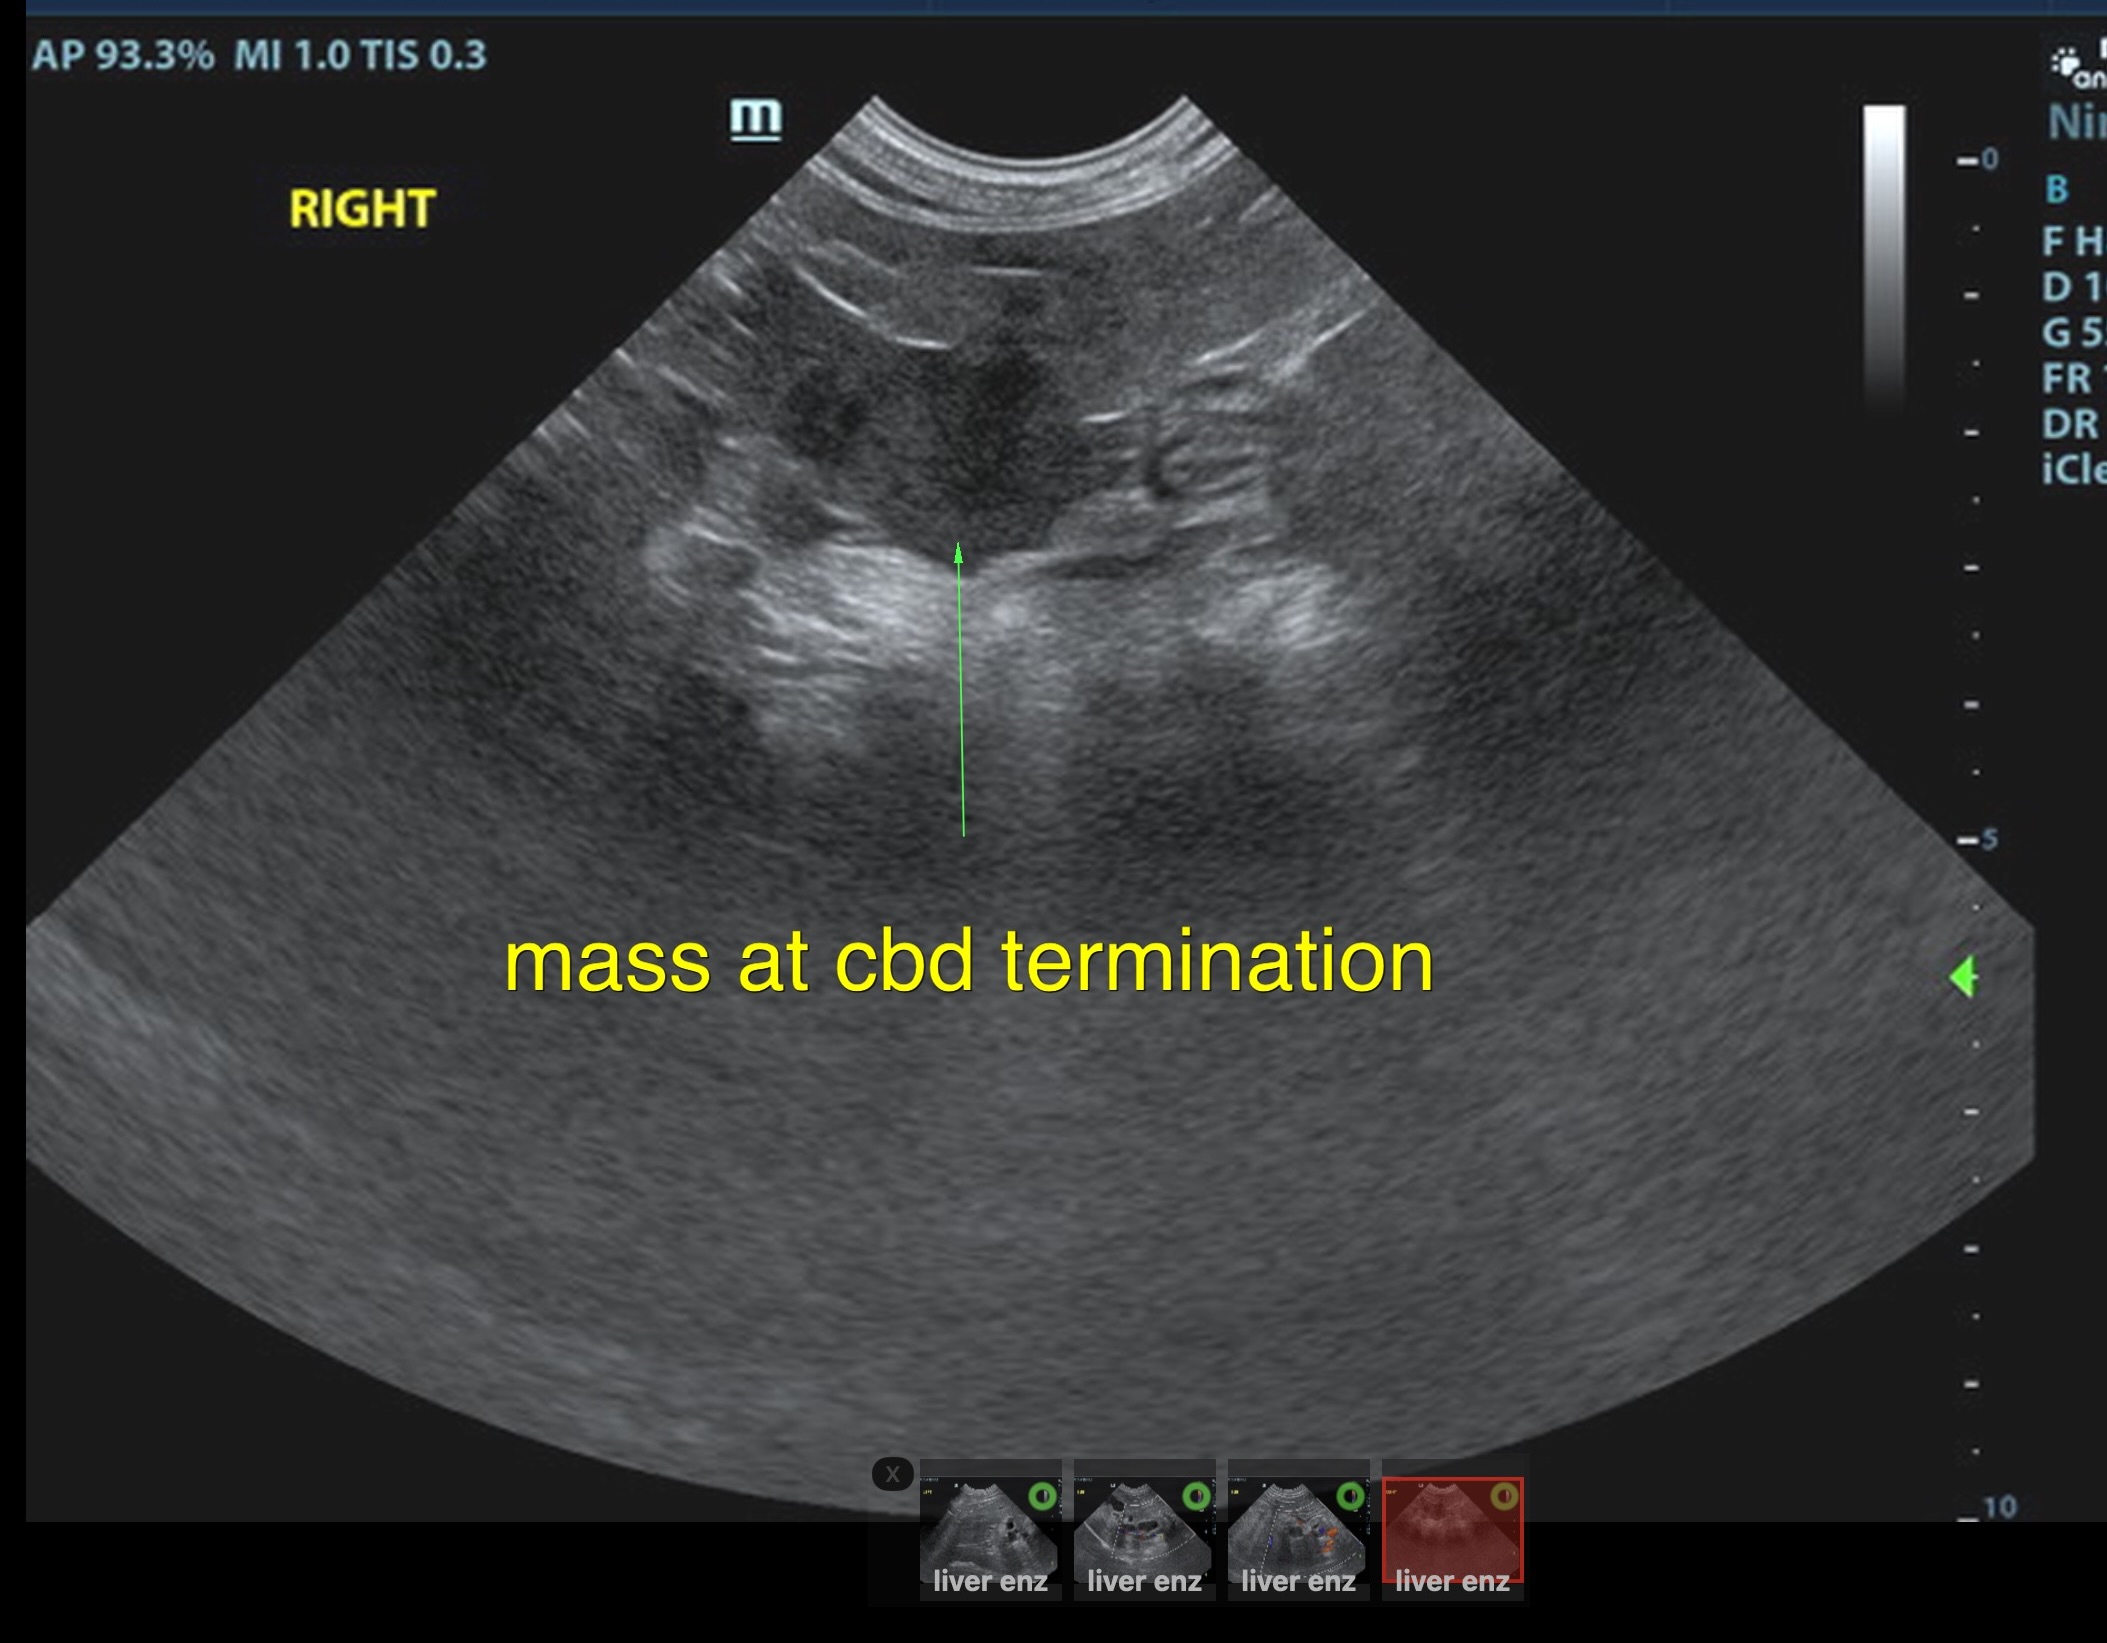

Local biliary duct dilation noted with post hepatic obstruction. Gallbladder was turgid. The common bile duct (CBD) was dilated with echogenic debris or possible tissue proliferation. The CBD measred 0.86 cm. An overt mass was noted at the common bile duct termination, measuring 2.0 cm. Target-type nodules noted in the liver.